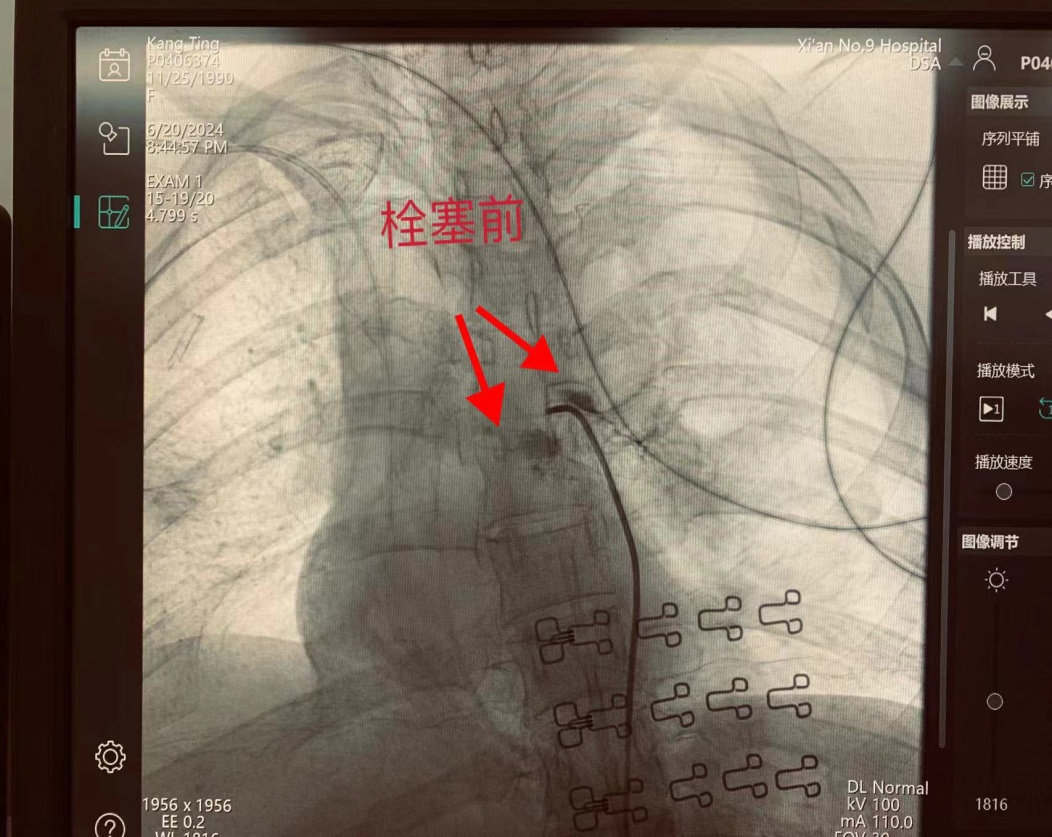

血管介入科马主任、彭教授立即为患者行动脉血管造影,提示左支气管近端可见造影剂外溢,找出靶血管进行栓塞止血。患者生命体征平稳转送患者至重症医学科继续治疗。